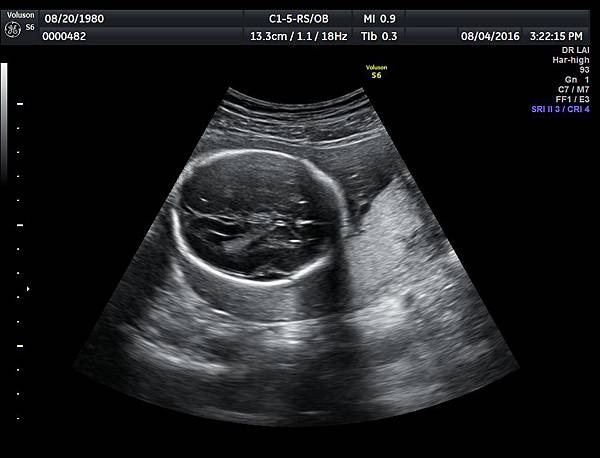

2016年8月4日在執行胎兒高層次超音波檢查時,我發現胎兒腦部的CSP(cavum septum pellucidum)很不清楚(附圖1~4),遇到這種情況,需要仔細評估胎兒腦部的駢胝體,因為CSP的天花板是駢胝體,CSP不明顯時,要合理的懷疑駢胝體沒有發育,或駢胝體下方有長東西(例如lipoma),駢胝體是連接左右大腦的神經纖維所組成。